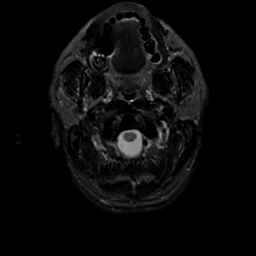

MR Study #22, December 1, 1991 -- Slice #0